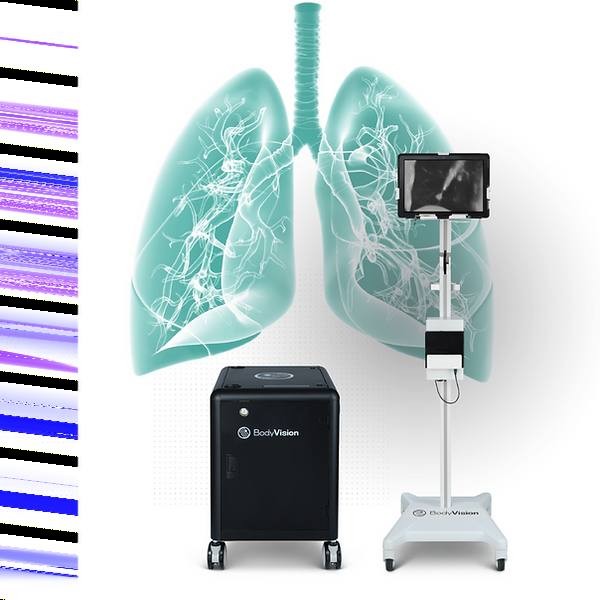

这是全球首款利用AI和AR技术的肺结节定位设备

项目类型

医疗器械区

起投金额

23000USDT

每日释放:0.82

释放周期:189 天

已购: 3913

剩余: 0

LungVision|Body Vision Medical

项目类型

器械质押区

起投金额

300000USDT

每日释放:1.2

释放周期:160 天

已购: 500

剩余: 0